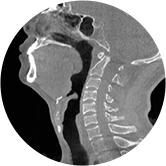

頸椎